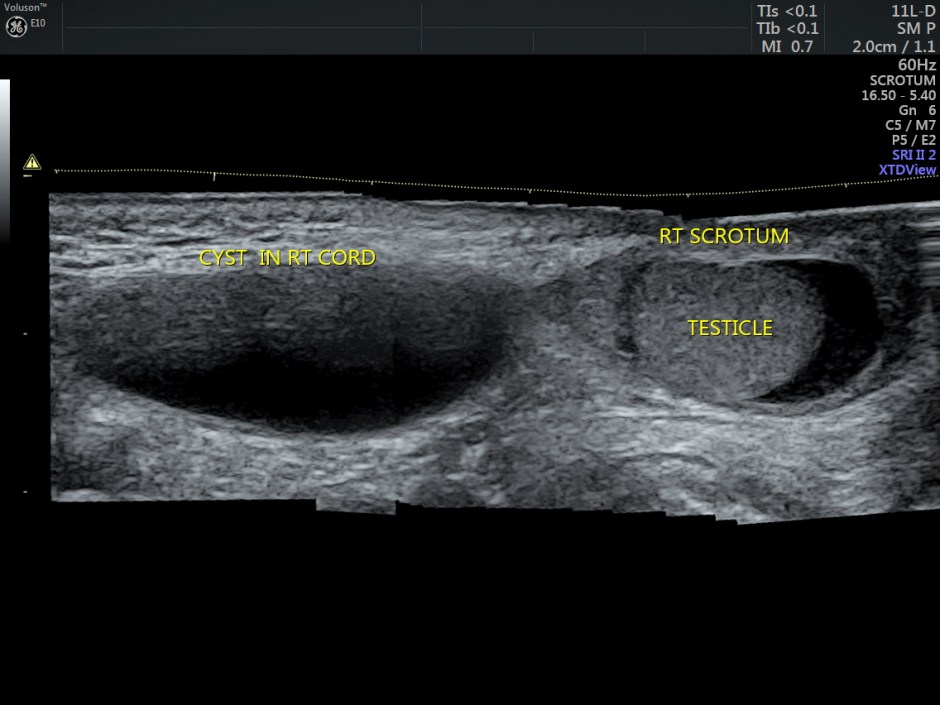

Ultrasound showed the two testicles in the scrotal sac and a cystic swelling above the right testis, distinctly separate from the same. Both the testicles appeared to have normal echotexture.

Panaoramic view of the same is given below.